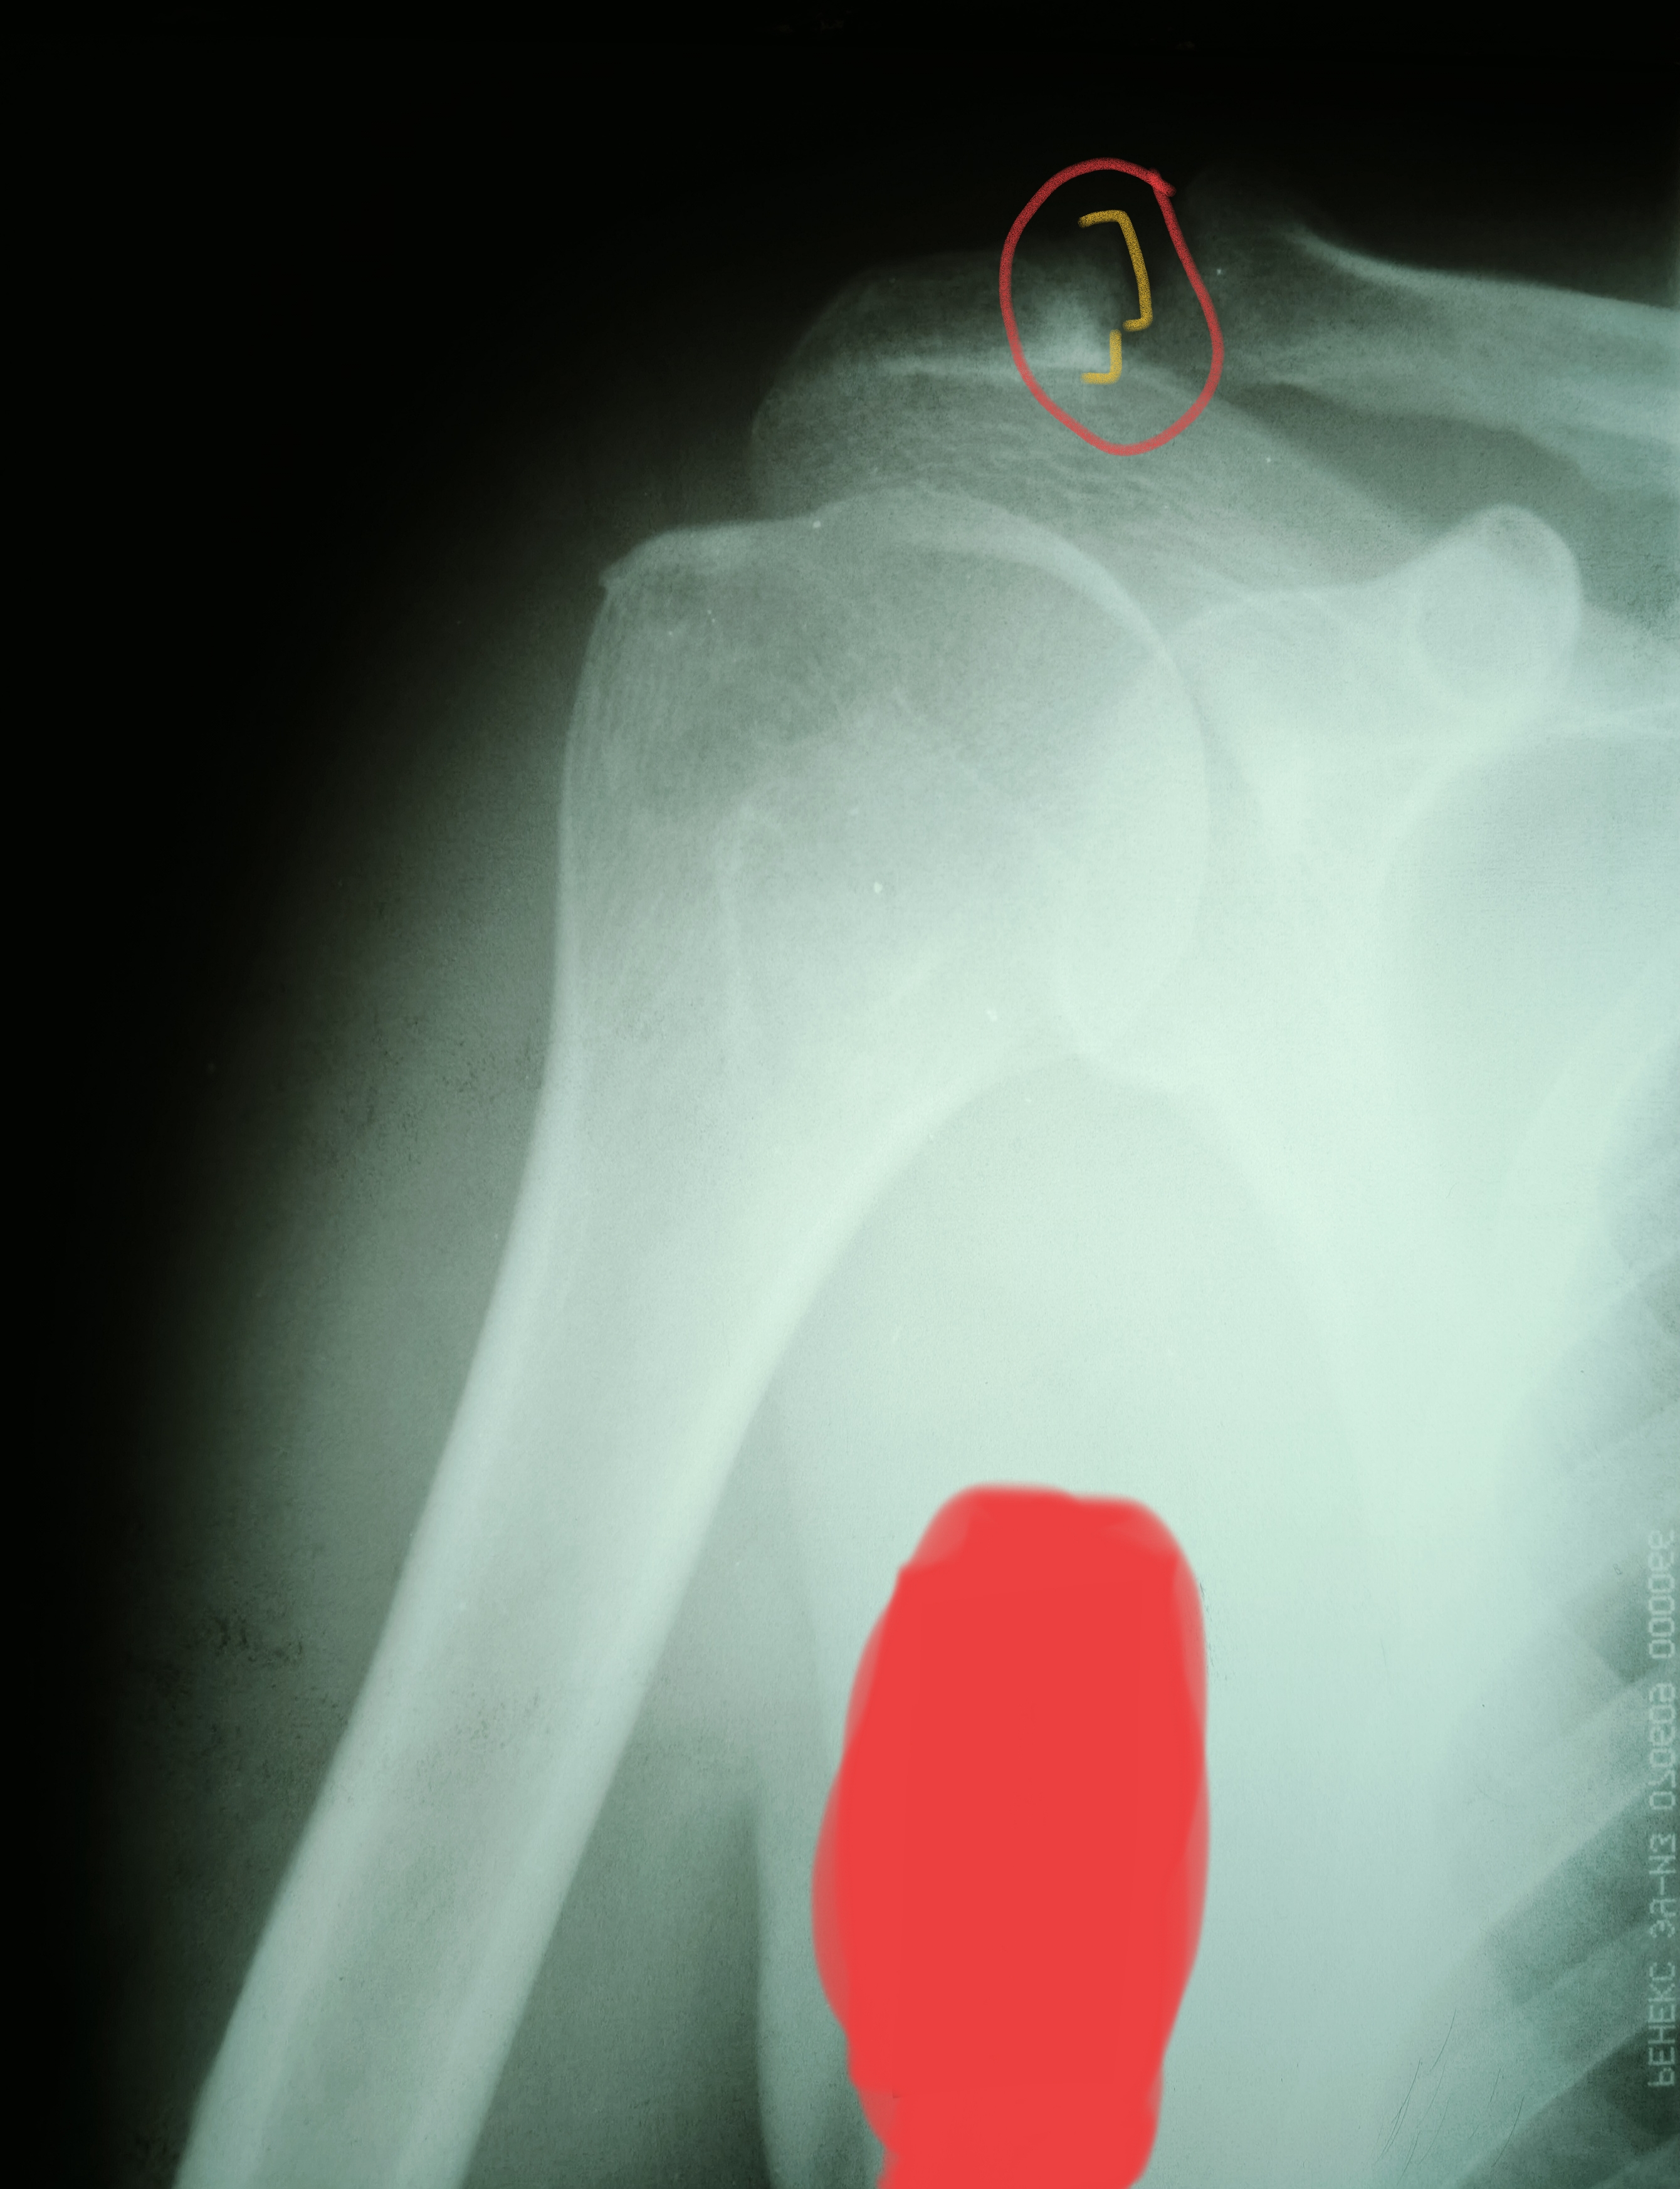

Акромион болит

Акромион болит 115 фотографий